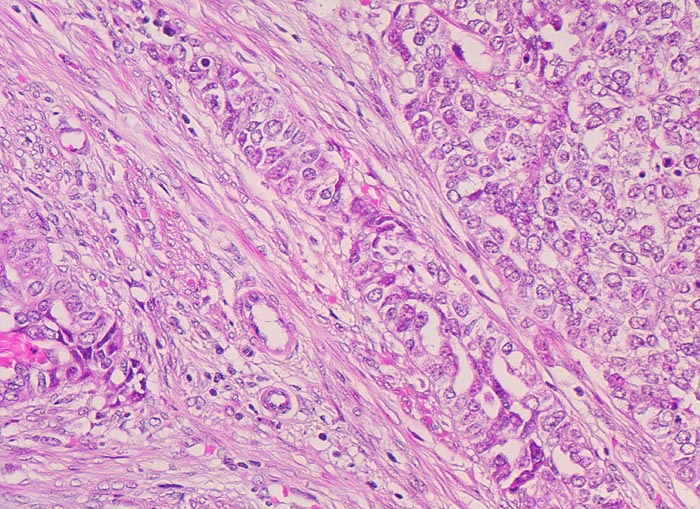

PathoPic – image database / PathoPic ID 4444 - endometrioides Adenokarzinom: Invasion des Myometrium

endometrioides Adenokarzinom: Invasion des Myometrium

Solide Tumorzellverbände infiltrieren die glatte Muskulatur des Myometrium. Die Tumorzellen haben grosse runde vesikuläre Kerne und wenig Zytoplasma.

Exophytischer, in das Uteruscavum hineinragender, weicher fokal hämorrhagischer Tumor ausgehend von der Uterushinterwand. Das Tumorgewebe infiltriert die innere Hälfte des Endometriums.